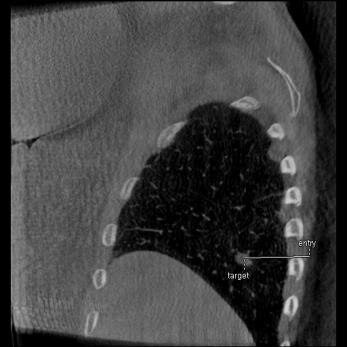

Pianificazione

Guida

Valutazione